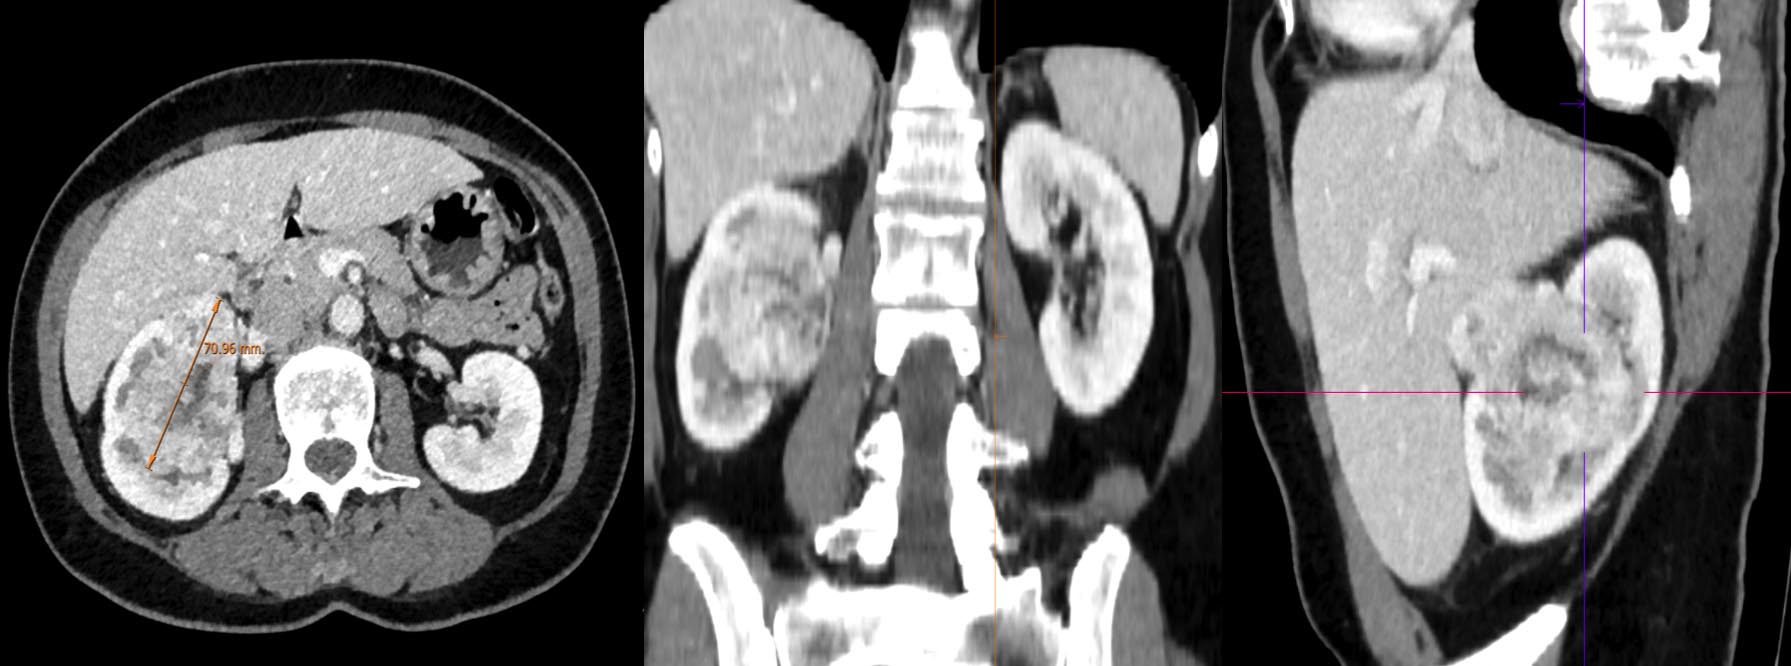

Se realizó BAG de mama con diagnóstico AP de neoformación de bajo grado citológico, de hábito epitelioide, con cambio de célula clara, con morfología e inmunofenotipo compatible con carcinoma en el material remitido.

Perfil inmunohistoquímico ampliado: expresión en las células epiteliales atípicas para RCC, CD10 (clon 56C6) (inmunotinción intensa) y PAX 8 (tinción nuclear); con negatividad para CK-7 (clon OV-TL12/30), HER 2, HMB45 (clon HMB45), Melan A (clon A103) y Actina (clon 1A4) (remarca la red vascular sinusoidal).

- A. Realizaría una BAV con ecografía para quitar la lesión del todo.

- B. Realizaría una TC toracoabdominopélvica con contraste.

- A. Tumoración primaria de mama con metástasis suprarrenales.

- B. Metástasis mamaria de carcinoma renal de células claras.

- C. Fibroadenoma y carcinoma renal de células claras.

- D. Tumoración primaria de mama con metástasis renal.

- E. Tumoración primaria de mama con diseminación ganglionar.